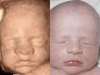

Antes y Después Antes y Después Boxeando Feto de 16 Semanas Feto de 21 Semanas